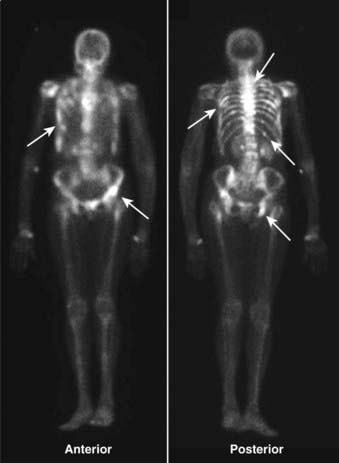

image In most instances, the entire body is imaged about 2 to 4 hours after injection, either by producing one image of the whole body, multiple spot images of particular body parts, or both. Anterior and posterior views are frequently obtained because each view brings different structures closer to the gamma camera for optimum imaging, e.g., the sternum on the anterior view and the spine on the posterior view.

image Unlike the convention used for viewing other studies in radiology, the patient’s right side is not always on your left in nuclear scans. This can be confusing, so make sure you look for the labels on the scan (Fig. 1).

image

Figure 1 Normal bone scan.

Anterior and posterior views are frequently obtained, since each view brings different structures closer to the gamma camera for optimum imaging, e.g., the sternum on the anterior view (solid white arrow) and the spine on the posterior view (dotted white arrow). Notice that the kidneys are normally visible on the posterior view (white oval). Unlike the convention used in viewing other studies in radiology, the patient’s right side is not always on your left. On posterior views, the patient’s right side is on your right. This can be confusing, so make sure you look for the labels on the scan. In many cases a white marker dot will be located on the patient’s right side (white circles).

Metastatic bone disease usually presents with a pattern of multiple, asymmetric focal areas of increased uptake (“hot spots”) on bone scans. Even lytic metastases (e.g., those caused by bronchogenic carcinoma) usually produce enough osteoblastic response to be positive on a bone scan (Fig. 2).

Figure 2 Metastases to bone.

Metastatic bone disease usually presents with a pattern of multiple, asymmetric focal areas of increased uptake (hot spots) on bone scans (white arrows). Even lytic metastases, e.g., those caused by bronchogenic carcinoma, usually produce enough osteoblastic response to be positive on a bone scan. This patient had metastatic breast carcinoma and had diffuse skeletal metastases including the ribs, pelvis, and spine.